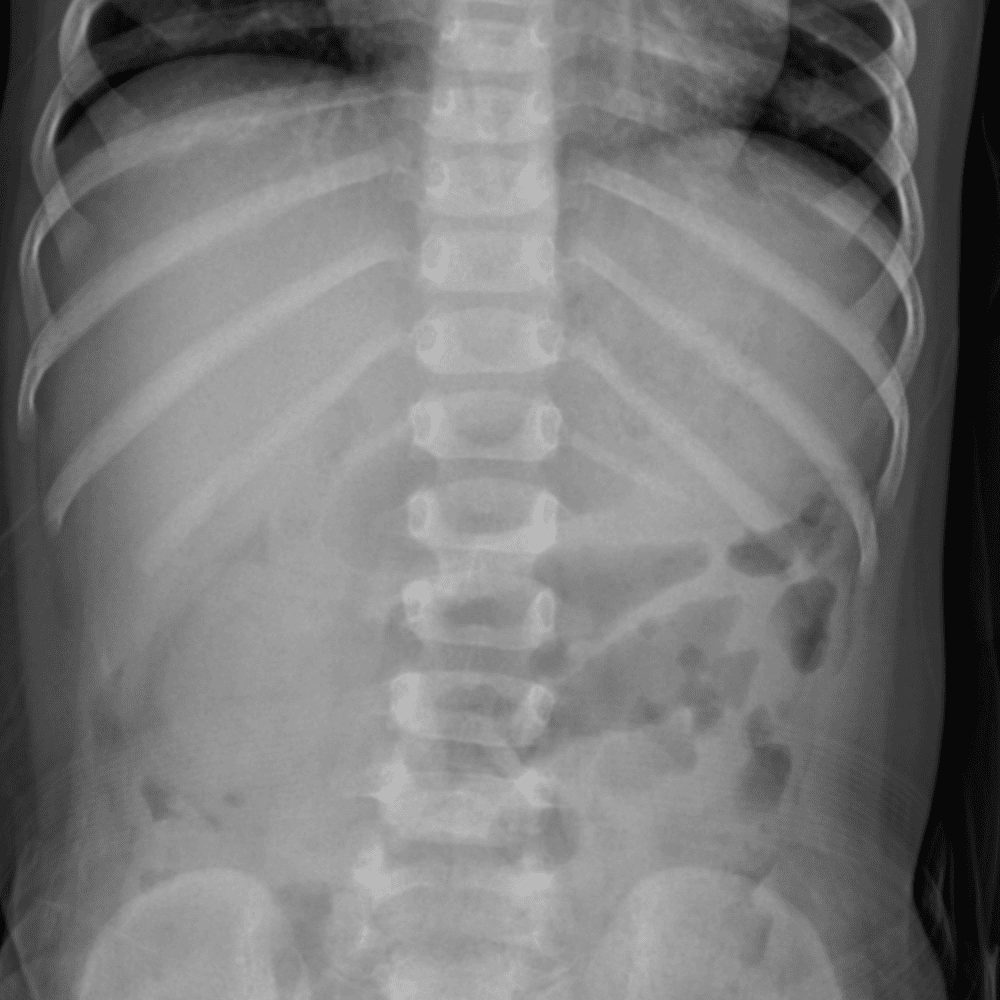

Peds Abdomen

Practice

Simulates call by including subtle or difficult cases and some normals.

30 cases